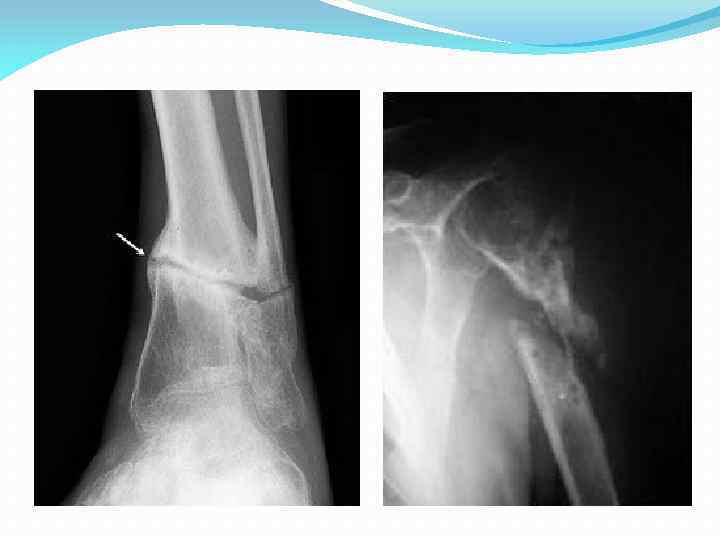

Классификация По механизму развития: 2. Атрофия от давления (сдавления) возникает при длительном давлении на орган опухоли, камня, увеличенного в размерах другого органа и т. п.